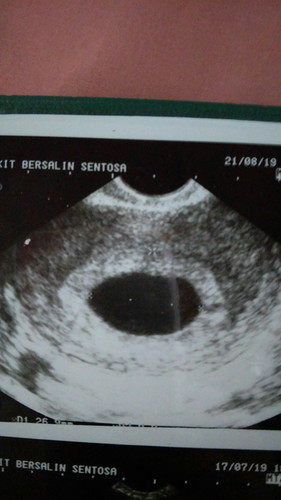

Pagi bunda.. Bagi pengalamannya ya apa ada disini yg usia kandungan waktu di USG 7 minggu dan divonis hamil kosong? Atau mmg belum kelihatan? ?ini foto hasil USG sy kemarin. Terimakasih bunda.

Baca lagiTerimakasih utk smua bunda yg sangat membantu sy dan suami. Walaupun pd akhirnya ttp harus ada tindakan bunda. Senin kemarin saya ke dokter ke3. Dokter yg mmg terkenal handal. Dr penjelasan beliau, sma bun vonisnya hamil kosong (BO). Dgn usia kehamilan sya, kantong sudah smakin besar akn tetapi isinya mmg tdk ada bun. Kalaupun nanti ada, dr dokter ad kecemasan umur janin ga ssuai dg umur kandungan yg sharusnya. Kalau nanti dpertahankan malah ada resiko2 trtentu bun. Jd sya dan suami putuskan utk ambil tindkan vakum bun.doakan ya bunda jumat ini tindakannya. Smoga smua lancar. Harapan kami jg bunda smoga ad keajaiban saat vakum nanti. Terimakasih ya untuk smua bunda yg sudah mmberikan support utk kami.

Bunda saya juga 10w kemarin persis seperti hasil usg bunda rahim saya. Trus dokter mendiagnosa kemungkinan BO. Saya takut dan cemas. Padahal saya tdk ada flek bun. Jadi saya berncana ikut cara bunda juga 1 bulan lagi baru usg bun

Saya juga waktu hamil 7w di usg dan hasil usgnya sma sprti bunda kaya gitu..trus kata dkternya bilang ini curiga hamil ektopik trus ada cairan disekitar rahim. Krena saya khawatir dan tkut bbrapa hari slnjutnya saya cek lgi ke dkter yg brbeda dan hasilnya baik2 saya ttpi utk uk 7w msh brupa kantng khamilan..dan ketika sya periksa lgi diusia kehmilan 11w alhamdulillah udh ada janin dan detak jantunya

Baca lagiSama bun.. saya sedang hamil 7 minggu masih kosong.. sedih banget.. tapi banyak ko yang mengalami bun.. ditunggu aja mudah2an babynya cepet terlihat.. dan positif thinking.. kata teman disaranin transvaginal aja.. soalnya sodaranya ada yg berkali kali usg ga keliatan karena perutnya tebel nanti aja kalau udah 10 mingguan.. kata dokter jg kalau bayi ga berkembang perlahan akan keluar bun..